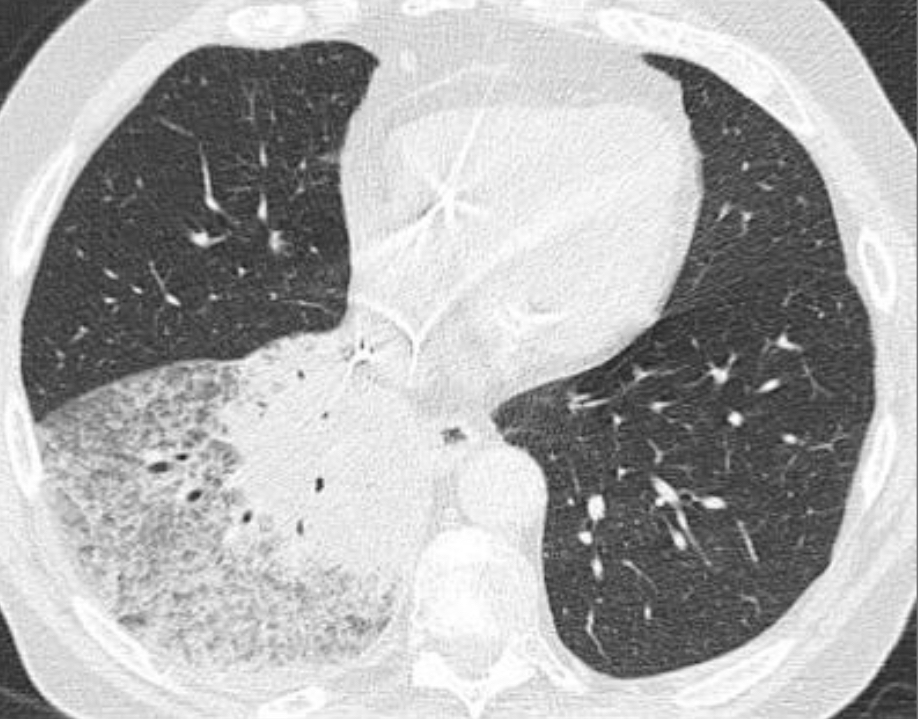

50M w/40 year smoking hx

RB-ILD

upper lung zone predominant process that features patchy ground-glass opacities and faint centrolobular nodules, as seen in this case. On a spectrum with DIP. Can see RB-ILD within 2 years of starting smoking, and treatment is cessation.